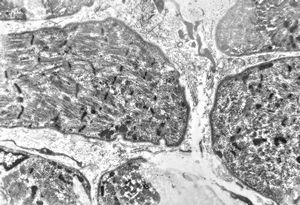

F,66y. | myositis